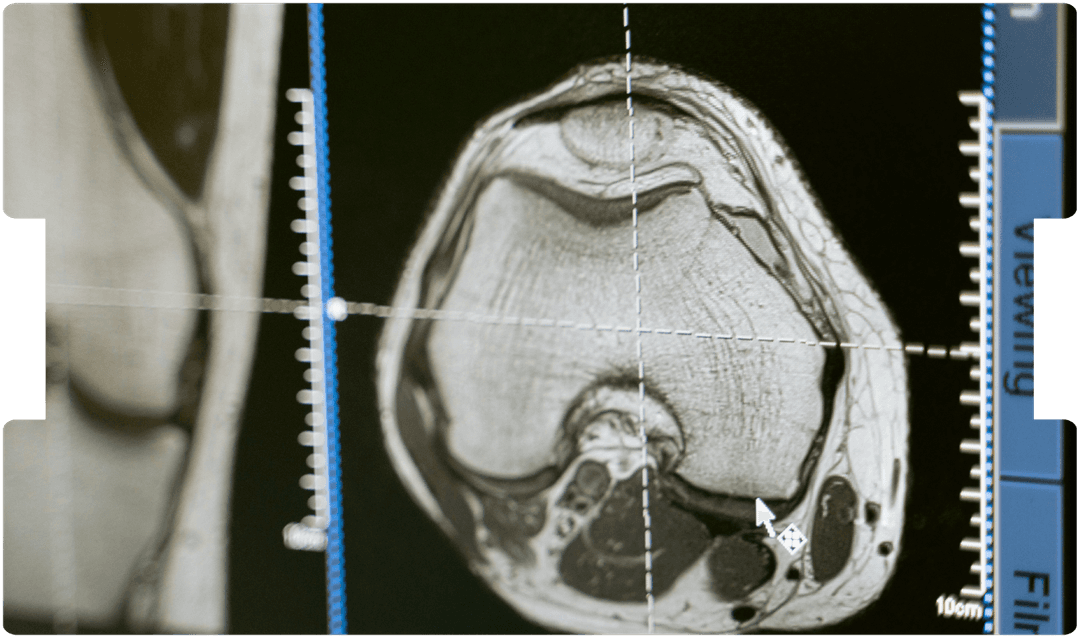

- MRI Imaging

Advanced neuroimaging is transforming TBI litigation. Discover how cutting-edge scans like DTI and rs-fMRI are offering solicitors powerful, objective proof where traditional imaging falls short.